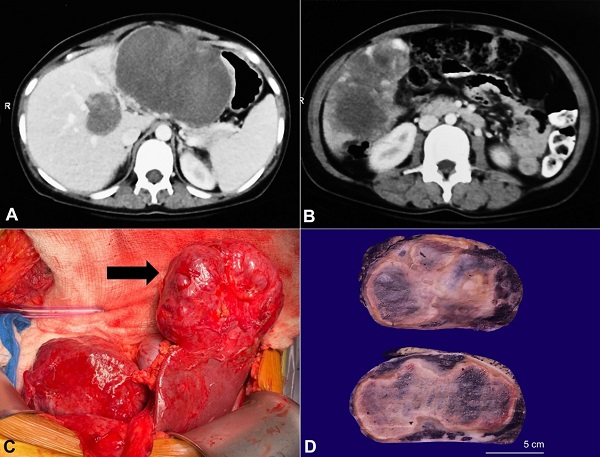

The contrast-enhanced computed tomography (CECT) scan showed an enlarged liver (liver span of 20 cm) with multiple heterogeneous hypodense lesions involving both the lobes. These lesions showed peripheral nodular enhancement. The largest lesion measuring 11×8×11.3 cm was located in the left lobe with medial extension in the gastrohepatic region abutting the gastric lesser curvature laterally, the antropyloric region inferiorly, and the body and the tail of the pancreas posteriorly (Figure 1A). Another large lesion sizing 10×7.5×8.2 cm was identified in the right hepatic lobe extending downwards to the pararenal space with irregular margins (Figure 1B). The hepatic and portal veins were patent. Thus, the diagnosis of multiple GCH was suggested. The imaging also revealed an enlarged spleen with normal attenuation; however, no focal lesion or other extrahepatic lesion was identified.

During surgical enucleation of the vascular masses, dense adhesions of the liver with both the anterior abdominal wall and transverse colon were noted (Figure 1C). The large lesions involving various anatomical segments were excised; A) a well-defined exophytic lesion (10×8 cm) involving segments VI and V abutting the gall bladder, B) the largest lesion (12×12 cm) completely replacing segments II and III, C) two smaller lesions (3×3 cm) involving segment IVb and segment VIII of the liver. A deep-seated lesion measuring 4×4 cm associated with the middle hepatic vein splaying was left in situ due to its proximity to these vessels.

The enucleation specimens from the right lobe, left lobe, and Segment VIII measured 8×6×4.5 cm, 9×7×5 cm, and 3.5×2×2 cm, respectively. The cut surfaces of all these specimens revealed well-encapsulated, dark red to tan-brown colored masses. These masses showed a firm to a spongy cut surface with a few perilesional cherry-colored honeycomb foci (Figure 1D).